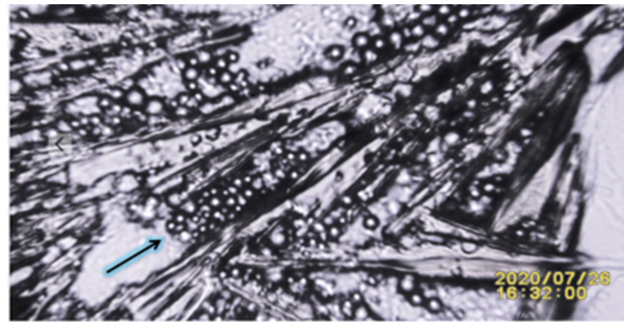

Figure 3

Figure 3 Amplified Image Showing the Process of Crystallization When Near Solid Human Tissue Attracting Particles (Lipids and Debris). Frame 1:15 of Video Recording Showing Hair Follicle Molecules Attracted Towards Evaporating Potassium Ferricyanide During Crystals Growth Stage. For Additional Video Details Please Link to: https://youtu.be/Kv1rRdNwuF4 |